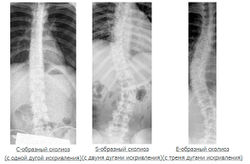

Классификация по форме искривления[править | править код]

- С-образный сколиоз (с одной дугой искривления).

- S-образный сколиоз (с двумя дугами искривления).

- Z, Е или W- образный сколиоз (с тремя дугами искривления).;